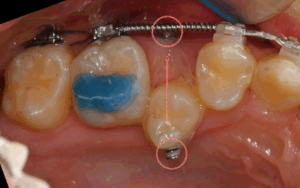

어금니에 임플란트를 심어놨어도 교정이 가능한가요? 중화동 치과

안녕하세요, 중화동 치과 김정은 원장입니다. ​ 오늘은 어금니에 임플란트가 심어져 있는 성인 교정 케이스에 대해 설명드리려 합니다. ​ 많은 분들이 상담을 오셔서 여쭤보는 질문 중 하나가, "치료를 받은 곳이 꽤…